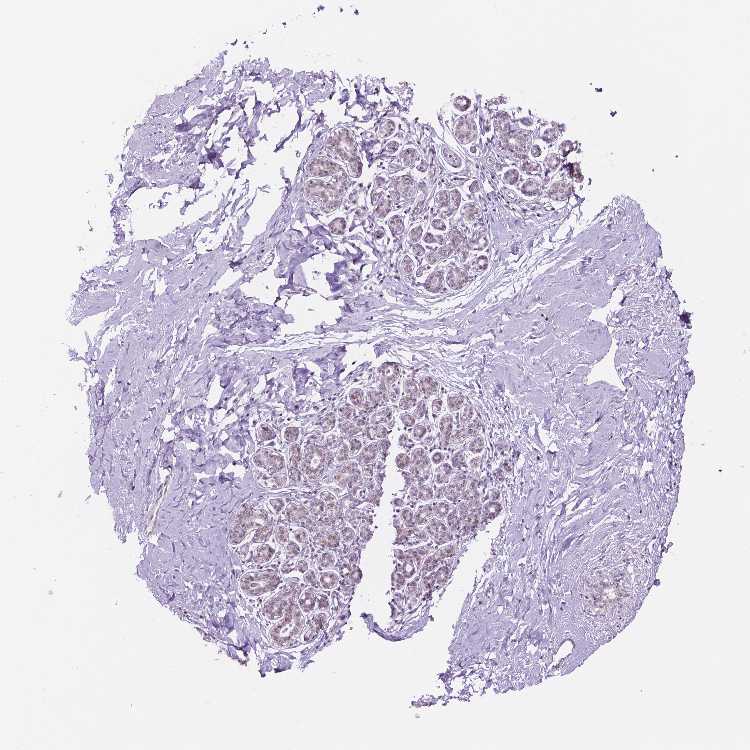

BREAST - Antibody stainingi

Antibody staining in the annotated cell types in the current human tissue is reported as not detected, low, medium, or high, based on conventional immunohistochemistry profiling in selected tissues. This score is based on the combination of the staining intensity and fraction of stained cells.

Each image is clickable and will lead to virtual microscopy that enables deeper exploration of all samples and also displays staining intensity scores, fraction scores and subcellular localization as well as patient and tissue information for each sample.

Antibody HPA050288Antibody HPA051168Antibody CAB072830

Adipocytes Not detectedNot detectedNot detected

Glandular cells Not detectedLowLow

Myoepithelial cells Not detectedNot detectedLow